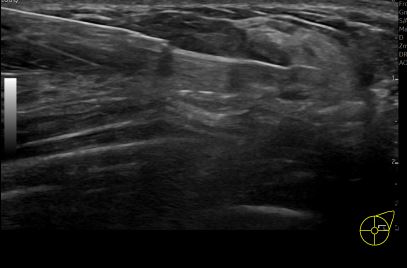

상기환자는 만져지는 멍울있어 검사위해  내원하신 30대 후반

여성분으로 의심스러운 좌측유방혹 조직검사 시행해 유방암으로 진단되었습니다